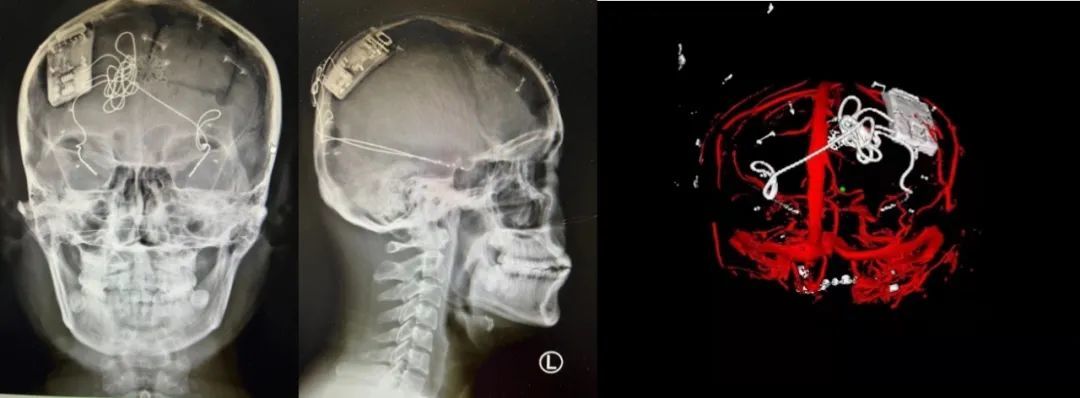

本次手術(shù)過程順利,術(shù)中刺激器各項(xiàng)指標(biāo)均工作正常,術(shù)后重建顯示電極位置精準(zhǔn),腦電信號清晰。患者為男性,入院后診斷為雙側(cè)顳葉癲癇,此類癲癇為開顱手術(shù)的相對禁忌癥,在藥物無法控制的情況下,傳統(tǒng)治療效果欠佳 。

術(shù)前經(jīng)過宣武醫(yī)院癲癇多學(xué)科專家團(tuán)隊(duì)詳細(xì)的臨床評估,包括視頻腦電監(jiān)測、頭顱磁共振及三維 CT 掃描、腦核醫(yī)學(xué)檢查等,全面評估了患者病情及致癇灶定位情況。

由于患者臨床診斷為雙側(cè)顳葉癲癇伴海馬硬化,無法通過致癇灶切除等傳統(tǒng)外科手術(shù)方式獲益,決定進(jìn)行閉環(huán)反應(yīng)性神經(jīng)刺激系統(tǒng)植入手術(shù)治療。并根據(jù)閉環(huán)神經(jīng)刺激技術(shù)特點(diǎn),為患者“量身定制”植入方案,尤其是電極植入位點(diǎn)和脈沖發(fā)生器固定部位等,為手術(shù)的順利實(shí)施奠定了良好基礎(chǔ)。

團(tuán)隊(duì)根據(jù)術(shù)前計(jì)劃,在手術(shù)機(jī)器人輔助下完成雙海馬長軸電極及 IPG 植入,術(shù)后重建顯示電極位置精準(zhǔn),腦電信號清晰。術(shù)后第二天,患者即下床活動,身體狀況恢復(fù)良好。